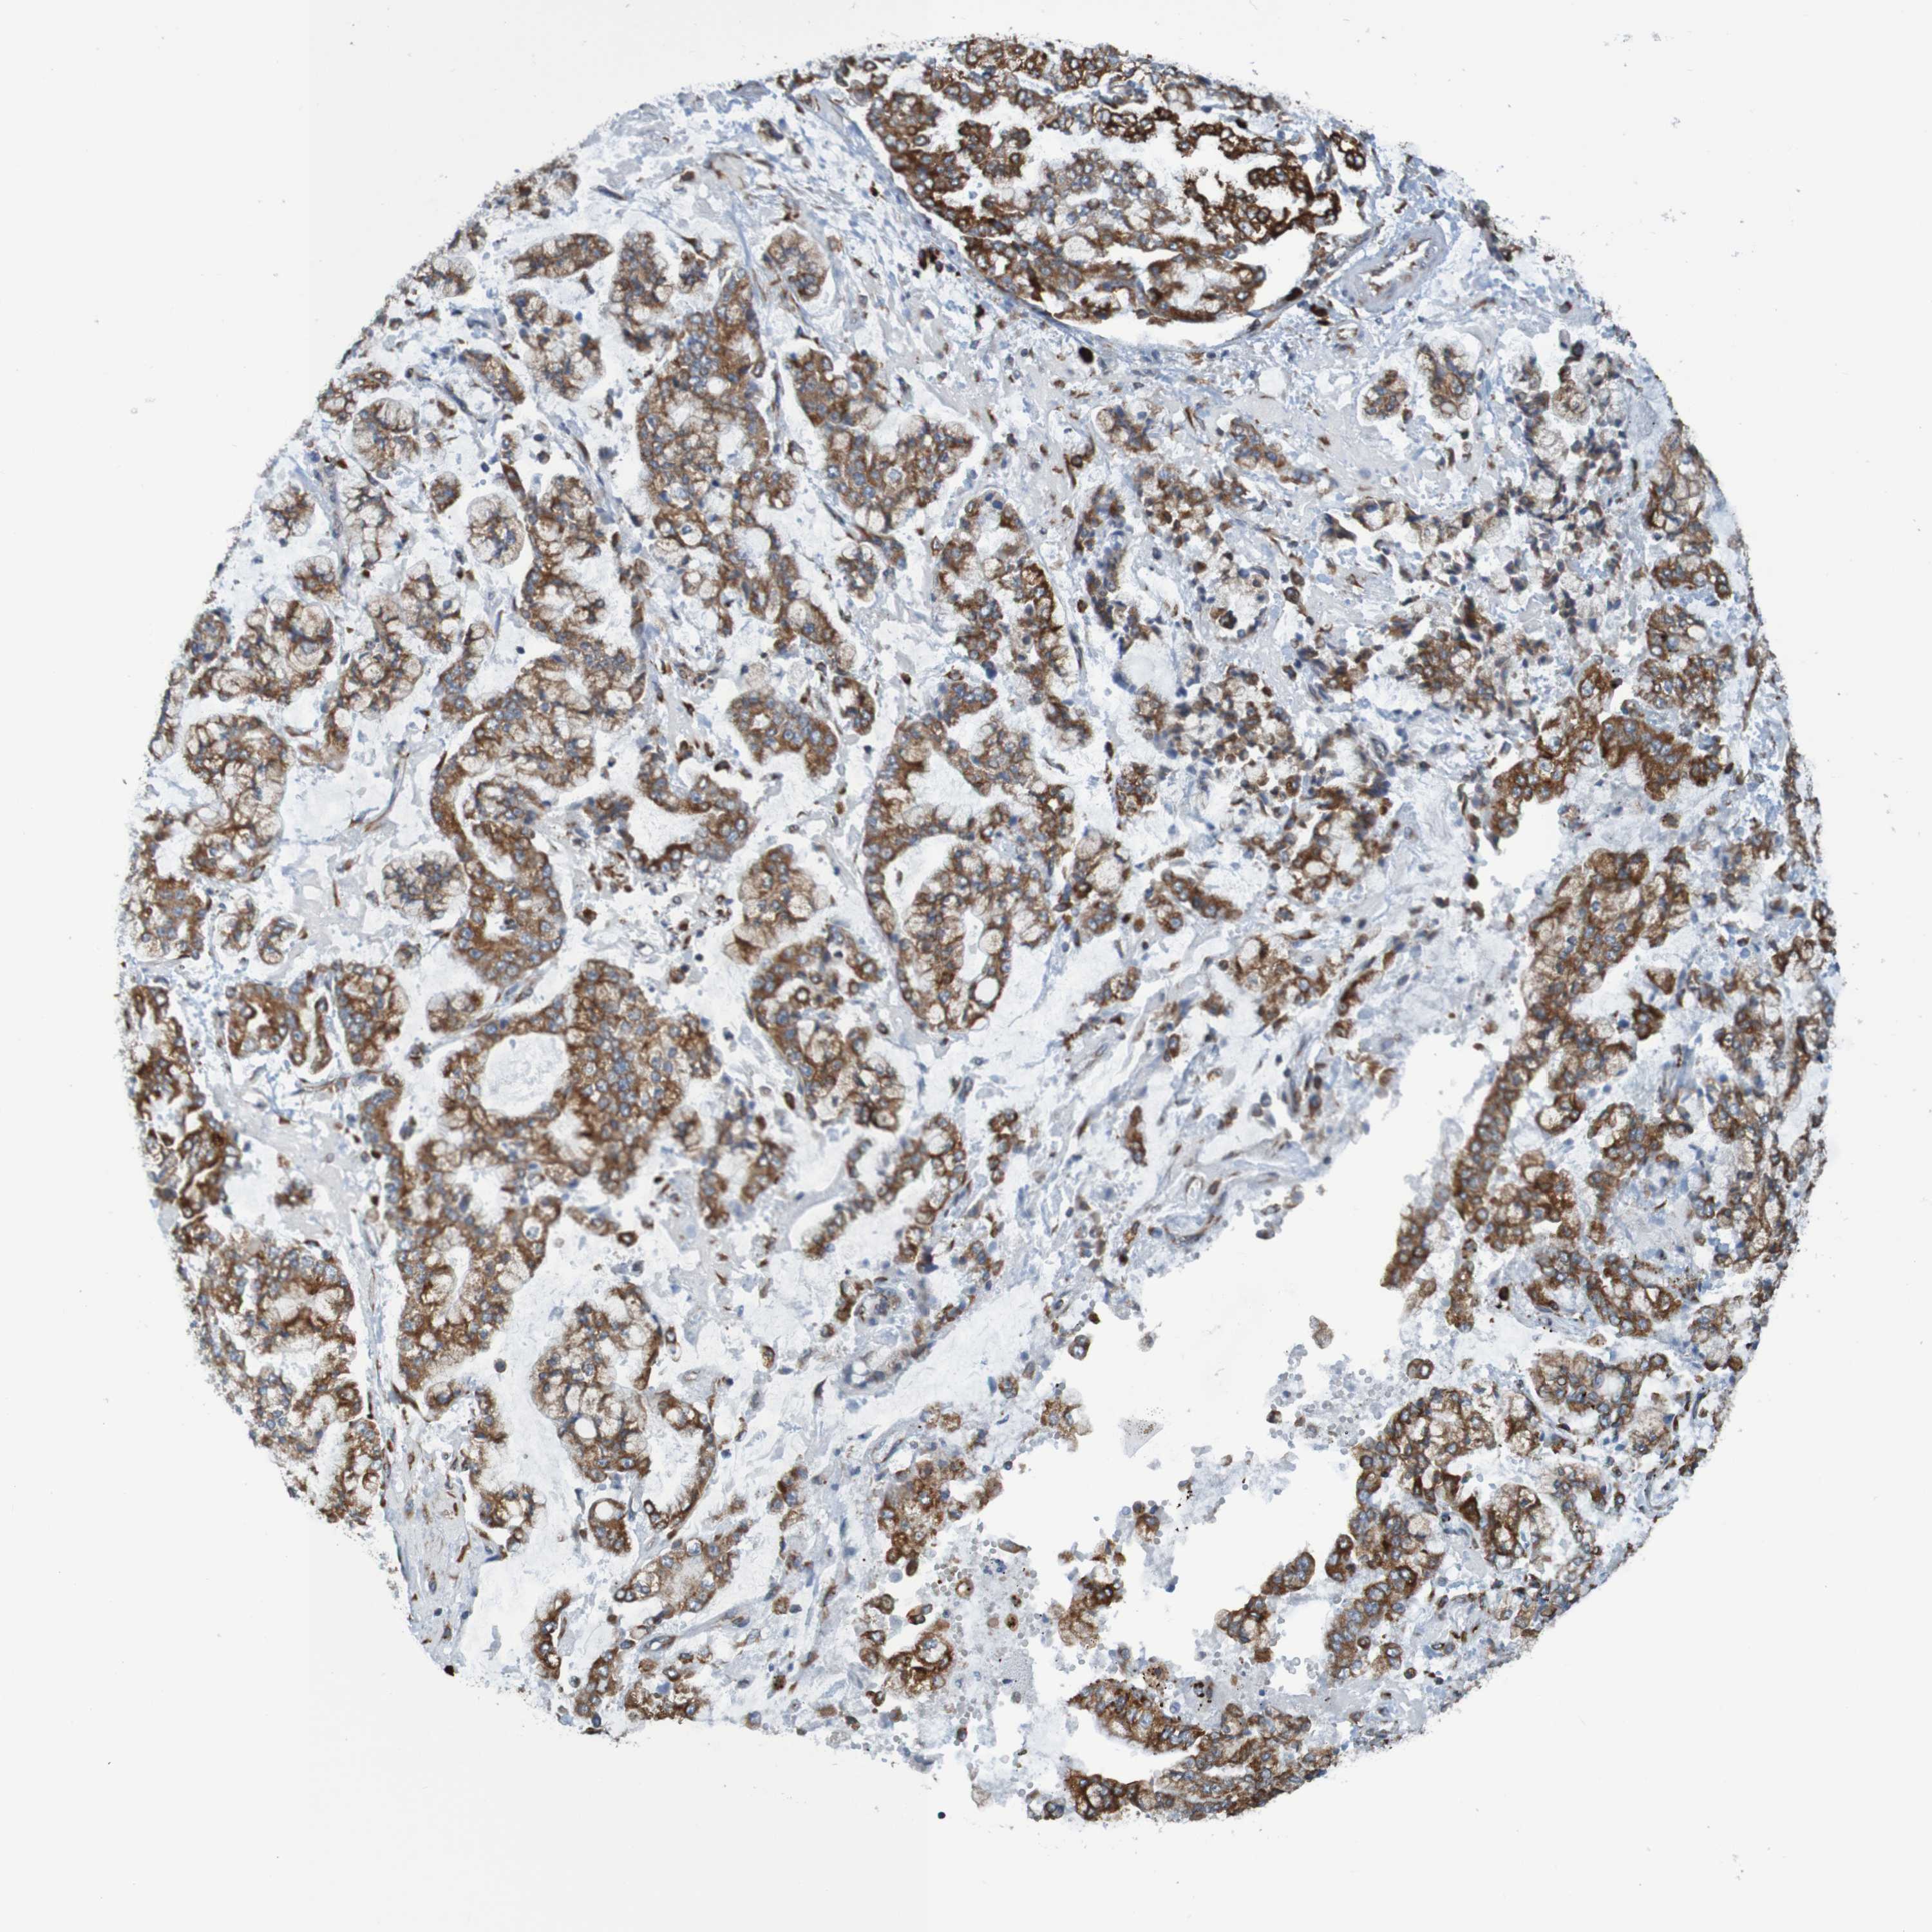

STOMACH CANCER - Protein expressioni

A mouse-over function shows sample information and annotation data. Click on an image to view it in a full screen mode. Samples can be filtered based on level of antibody staining by selecting one or several of the following categories: high, medium, low and not detected. The assay and annotation is described here.

Note that samples used for immunohistochemistry by the Human Protein Atlas do not correspond to samples in the TCGA dataset.

Antibody stainingi

Antibody staining in the annotated cell types in the current human tissue is reported as not detected, low, medium, or high, based on conventional immunohistochemistry profiling in selected tissues. This score is based on the combination of the staining intensity and fraction of stained cells.

Each image is clickable and will lead to virtual microscopy that enables deeper exploration of all samples and also displays staining intensity scores, fraction scores and subcellular localization as well as patient and tissue information for each sample.

Antibody HPA011276

Antibody HPA017062

Staining

High

Medium

Low

Not detected

Intensity

Strong

Moderate

Weak

Negative

Quantity

>75%

75%-25%

<25%

None

Location

Nuclear

Cytoplasmic/membranous

Cytoplasmic/membranous,nuclear

Adenocarcinoma, NOS

Adenocarcinoma, High grade